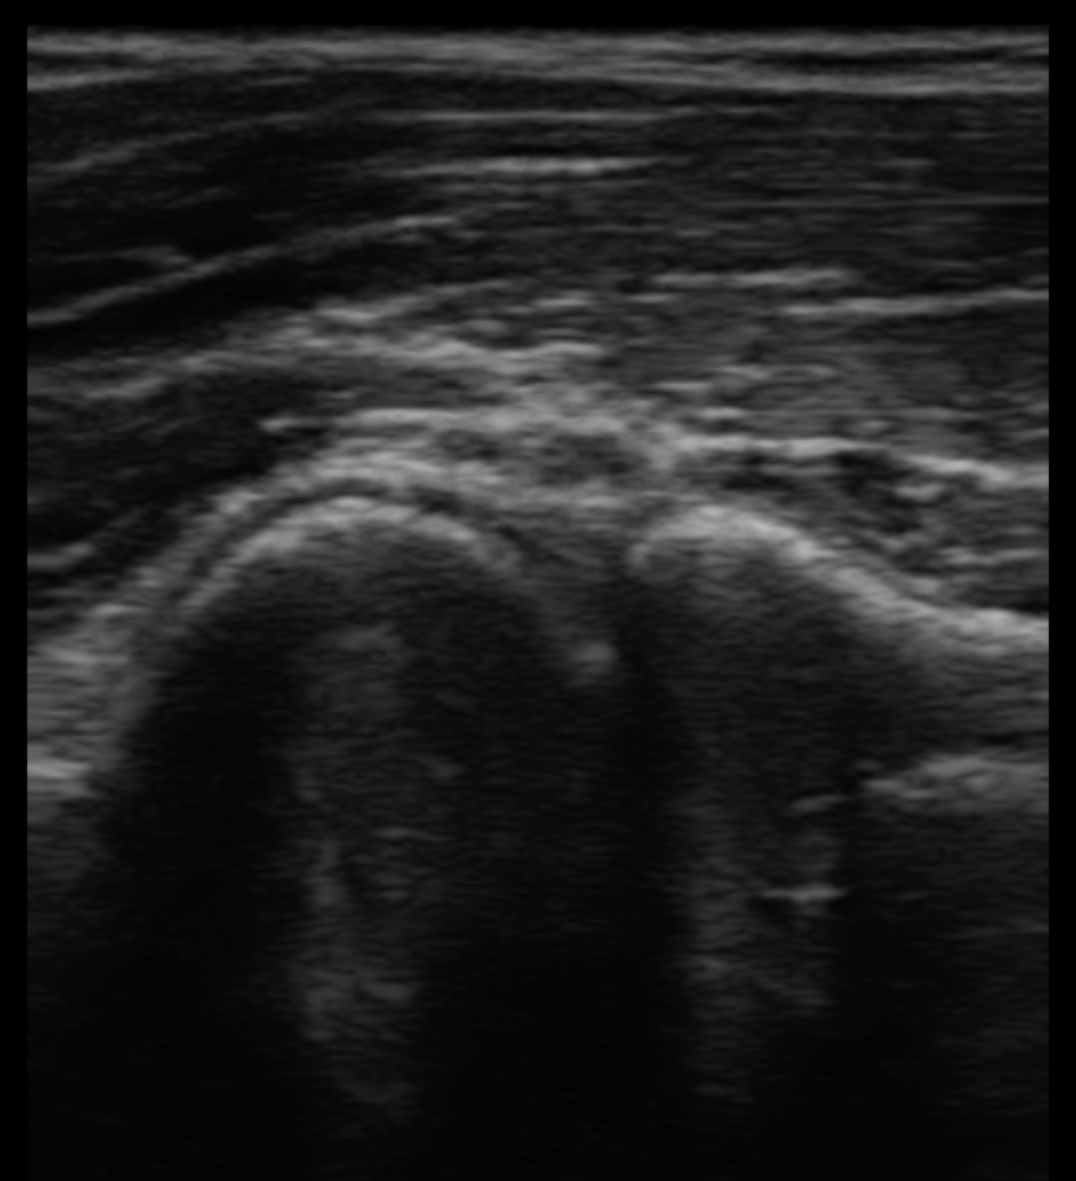

エコー検査でケガの状態を画像でチェック!

当院には最新型のエコー観察装置が入っていますので、骨折の有無や靭帯・筋肉の断裂、炎症度合いを逐一画像で確認できるため、正確な評価と治療効果の確認が行えます。 そのためより効率的に日常生活やスポーツへの復帰が可能となります。

画像での確認ができる為、患者様も状態を把握しやすく、安心して治療が行えます。